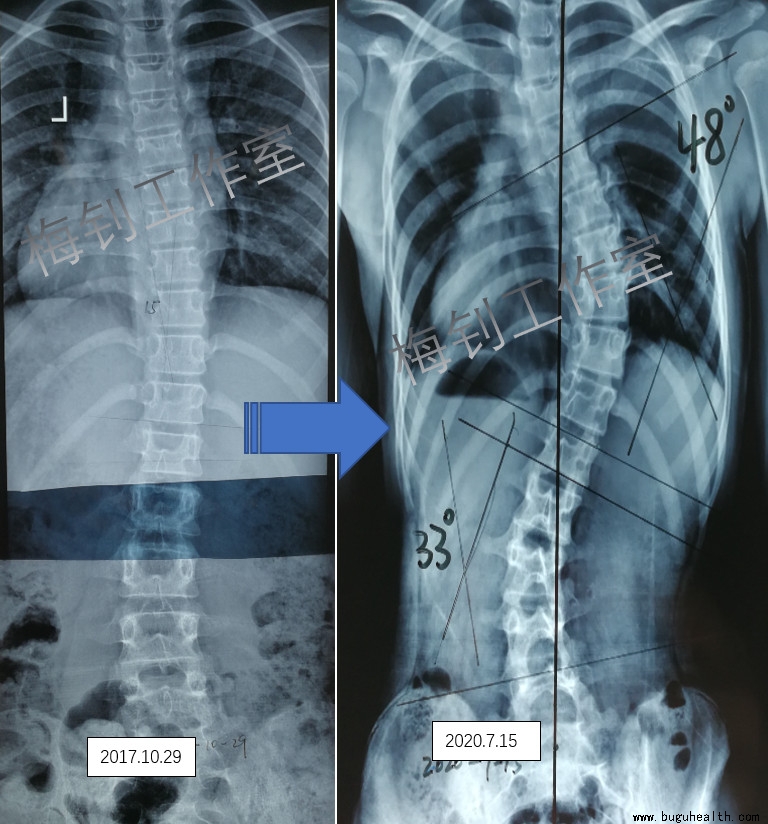

女孩,2017年10月发现脊柱侧弯,当时11岁,侧弯度数为15度,多次就医,被医生告知病情轻微,不需要干预。2020年7月,家长发现体表变化明显,再次就医后被告知需要马上手术。

以上病例,侧弯自然发展2年多,从15度加重到48度。从被告知不需要治疗,到后面直接要求手术,家长不能接受。开始尝试支具治疗。目前支具治疗10个月,虽然度数有所降低,但仍然需要坚持穿戴支具,一般需要戴到骨骼发育结束。当错失了最佳的治疗时期,支具治疗的周期也被延长。